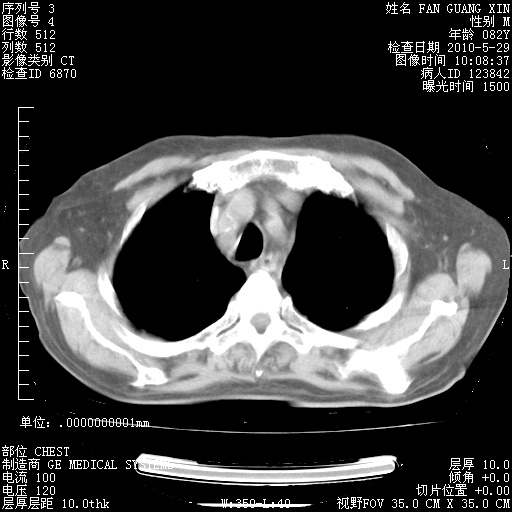

治疗3周后的肺部CT纵隔窗

再治疗10天后的肺部CT